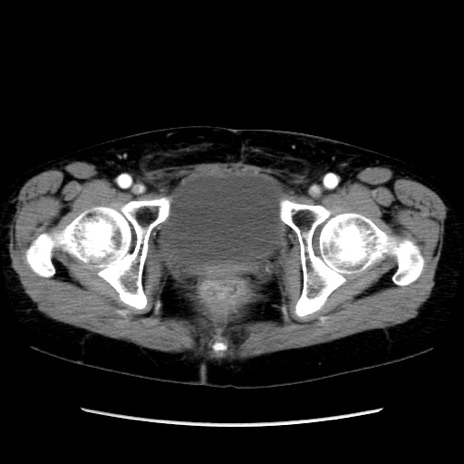

症例32(横断像)

【症例】40歳代 女性

【既往歴】子宮頚癌(広汎子宮全摘術、放射線療法)、腸閉塞